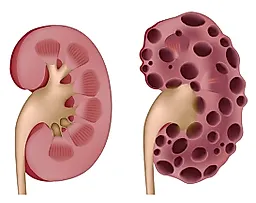

Простая киста почки — это доброкачественное образование, которое при ультразвуковом исследовании или на компьютерной томограмме имеет округлую форму, четкие границы и тонкую стенку. Простая киста почки неэхогенна при ультразвуковом исследовании, на компьютерной томограмме она имеет низкую плотность (< 20 единиц Хунсфилда) и не заполняется контрастным веществом.

Сложная киста почки имеет один или несколько признаков, которые могут быть характерны для злокачественного новообразования, например внутренние перегородки, кальцификаты в стенках кисты и внутренних перегородках, высокую плотность или неоднородность внутреннего содержимого кисты, неровные края или участки усиления контрастности при КТ. Сложные кисты с перегородками и кальцификатами в большинстве случаев являются доброкачественными образованиями, тогда как другие перечисленные признаки более характерны для почечно-клеточного рака.